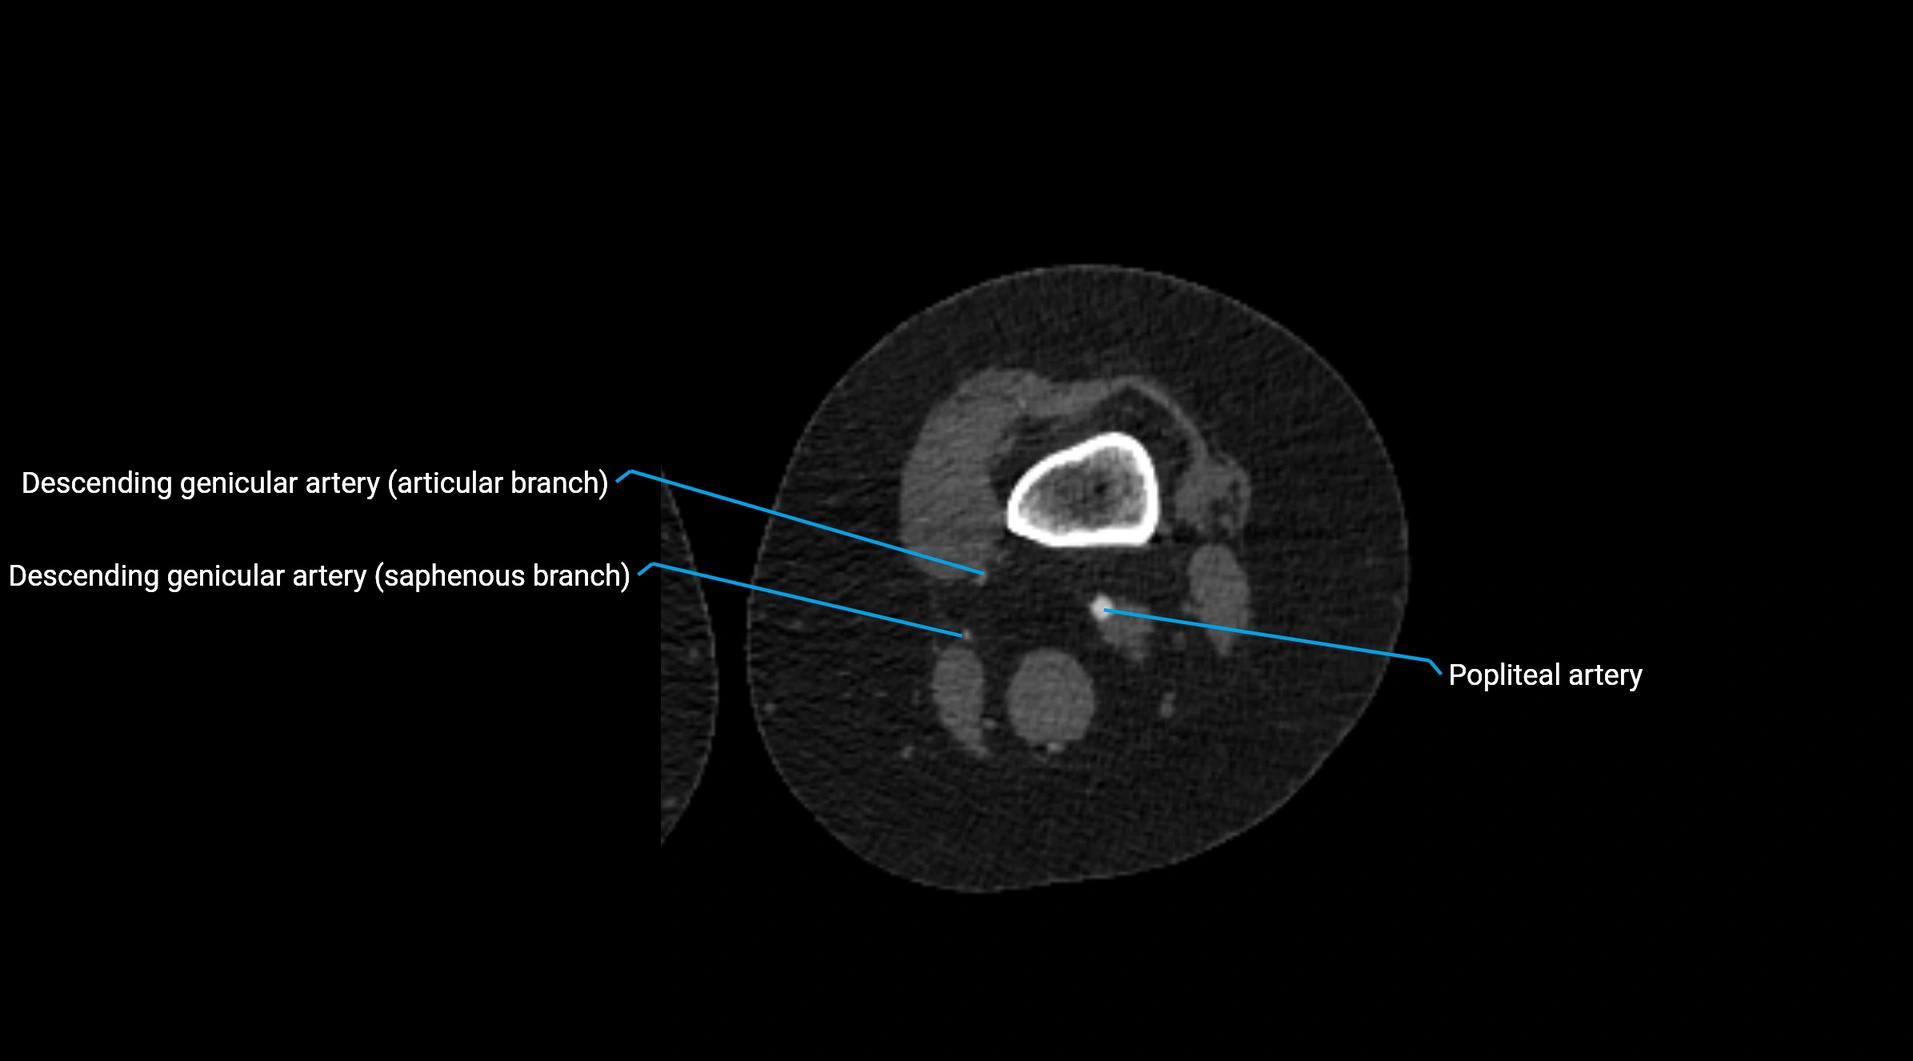

CT images

image

Contrast-enhanced CT (CTA):

• Gold standard for abdominal aortic imaging

• Provides excellent detail of lumen, wall, aneurysm, thrombus, and branch vessels

• Multiplanar and 3D reconstructions help in aneurysm measurement, stent graft planning, and dissection evaluation